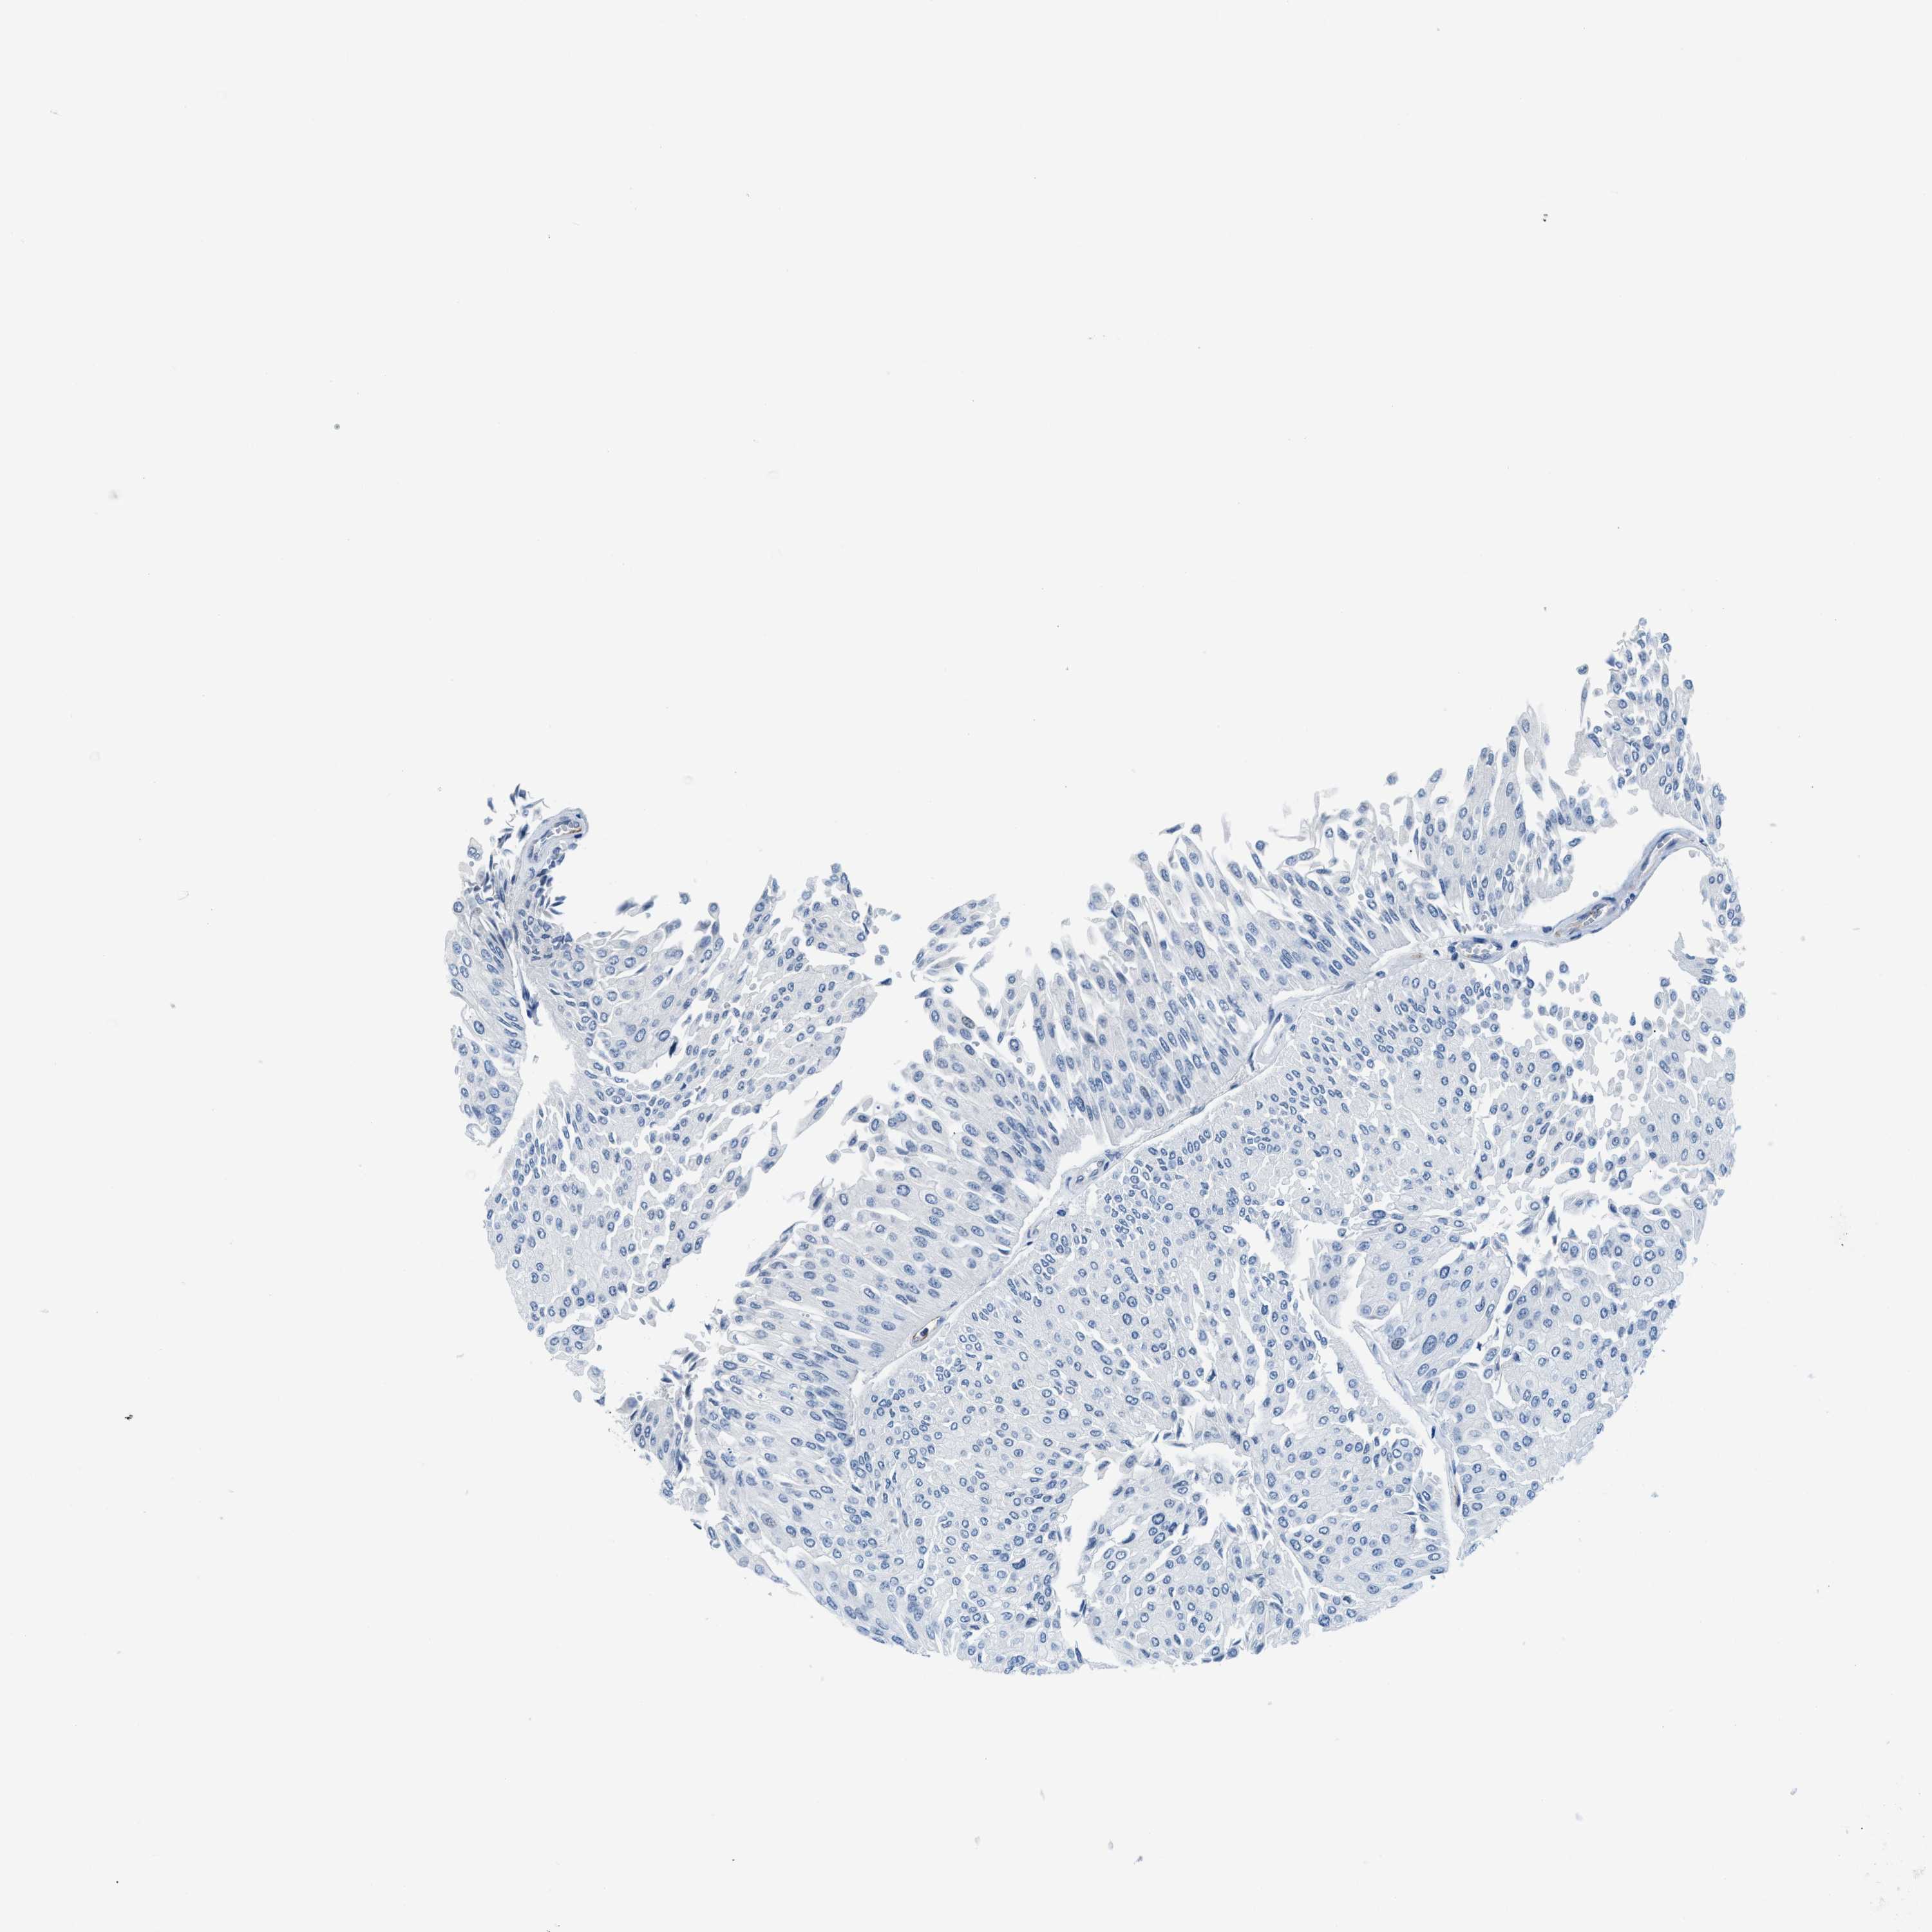

UROTHELIAL CANCER - Protein expressioni

A mouse-over function shows sample information and annotation data. Click on an image to view it in a full screen mode. Samples can be filtered based on level of antibody staining by selecting one or several of the following categories: high, medium, low and not detected. The assay and annotation is described here.

Antibody stainingi

Antibody staining in the annotated cell types in the current human tissue is reported as not detected, low, medium, or high, based on conventional immunohistochemistry profiling in selected tissues. This score is based on the combination of the staining intensity and fraction of stained cells.

Each image is clickable and will lead to virtual microscopy that enables deeper exploration of all samples and also displays staining intensity scores, fraction scores and subcellular localization as well as patient and tissue information for each sample.

Antibody HPA002027

Antibody CAB016782

Urothelial carcinoma, High grade

Urothelial carcinoma, Low grade

Adenocarcinoma, NOS